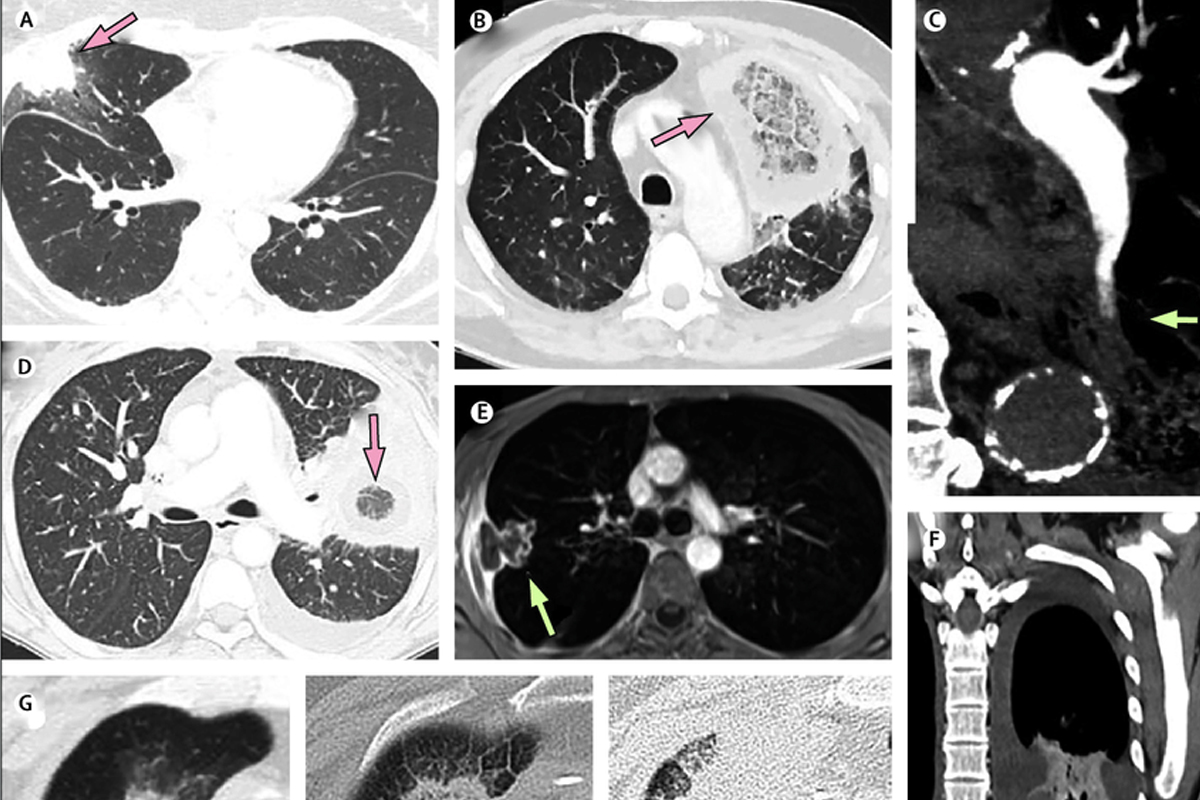

कल्याण, 11 मे : कोरोनापाठोपाठ कल्याण-डोंबिलवीकर (KDMC) म्युकरमायकोसीसच्या (Mucormycosis) कचाट्यातही सापडल्याचं पाहायला मिळत आहे. केडीएमसी (KDMC) हद्दीत या आजारावर उपचार घेणाऱ्या दोन रुग्णांचा (Two Patient Died) मृत्यू झाला आहे. तर आणखी सहा रुग्णांवर याठिकाणी उपचार सुरू असल्याची माहिती महापालिकेच्या मुख्य वैद्यकीय (CMO) अधिकारी डॉ.अश्विनी पाटील (Dr. Ashwini Patil) यांनी दिली आहे. गंभीर अशा करोना रुग्णांना उपचारासाठी वापरल्या जाणाऱ्या औषधाचे दुष्परीनाम रुग्णावर होत आहेत. त्यामुळं कोरोनानंतर होणाऱ्या म्युकरमायकोसिस आजाराने कल्याण डोंबिवलीत दोन बळी घेतले आहेत. ठाणे ग्रामीणमधले म्हारळ भागातील 38 वर्षीय तरूण तुकाराम भोईर आणि डोंबिवली पूर्वेकडील एका 69 वर्षीय बाजीराव काटकर या नागरिकाचा म्युकरमायकोसीस आजारानं मृत्यू झाल्याची माहिती पालिकेच्या आरोग्य विभागाकडून देण्यात आली. डोंबिवलीतील एम्स या खाजगी रुग्णालयात या रुग्णांवर उपचार सुरु होते. दरम्यान, या आजाराने ग्रस्त असलेल्या आणखी 6 रुग्णांवर उपचार सुरू आहेत. (वाचा- Mucormycosis चा विळखा, उपचारासाठी ठाकरे सरकार खरेदी करणार 1 लाख इंजेक्शन, हाफकिनला दिली ऑर्डर ) कोरोना रुग्णांवर उपचारासाठी गरजेपेक्षा जास्त वापरली जाणारी औषधे, मधुमेह ग्रस्त रुग्णाच्या शरीरात उपचारासाठी वापरल्या जाणाऱ्या औषधामुळं वाढणारं साखरेचे प्रमाण यामुळं अशा रुग्णांना म्युकरमायकोसीस आजार होण्याचे प्रमाण जास्त आहे. रुग्णांनी शरीरातील साखरेचे प्रमाण नियंत्रित ठेवावे तसेच डॉक्टरानी स्टेरॉइड सारख्या औषधाचा वापर गरजेनुसारच करावा असं आवाहन पालिकेच्या मुख्य वैद्यकीय अधिकारी डॉ अश्विनी पाटील यांनी केलं आहे. ठाण्यात आढळला पहिला रुग्ण ठाणे जिल्हा सामान्य रुग्णालयात एका 56 वर्षीय महिलेलाही हा आजार झाल्याचं समोर आलं. या महिलेला कोरोना झाला होता मात्र याच दरम्यान त्या महिलेची रोग प्रतिकार शक्ती कमालीची कमी झाल्याचे लक्षात आल्यानंतर या महिलेच्या काही वैद्यकीय चाचण्या करण्यात आल्या. या चाचण्यांचा अहवाल समोर आला. जिल्हा शल्यचिकित्सक डॉक्टर शुभांगी अंबाडेकर यांनी महिलेची तपासणी केली असता, महिलेच्या डोळे वर आलेले दिसून आले तर उजव्या डोळ्याची हालचाल होत नसल्याचे तपासणी दरम्यान लक्षात आले, तसंच महिलेच्या उजव्या डोळ्यावर प्रकाश टाकल्यानंतरही डोळ्याची कोणतीच हालचाल होत नव्हती. तर महिलेच्या सिटीस्कॅन, ओर्बिट ब्रेन सिटी स्कॅन चाचणी अहवालात देखील अनेक लक्षणे आढळून आले. उजव्या डोळ्याच्या मासपेशींना सूज आली होती तसंच इतरही अंतर्गत लक्षणे वैद्यकीय चाचणी अहवालात दिसून आले. या आधारे तसंच म्युकोरमायकोसिस या आजाराची सांगितली गेलेली लक्षणं या महिलेत आढळल्याने या महिलेला म्युकोरमायकोसिस असल्याचे जिल्हा रुग्णालयाच्या डॉक्टरांनी स्पष्ट केलं. (वाचा- Salute! चिमुरड्यांसह आई-वडिलांनाही झाला संसर्ग, तरी डॉक्टर आई बजावतेय कर्तव्य ) म्युकरमायकोसिस म्हणजे काय? म्युकरमायकोसिस दुर्मिळ असला, तरी नवा नाही. प्रतिकारशक्ती (Immunity) कमी असलेल्या, अतिदक्षता विभागात (ICU) असलेल्या, तसंच अवयव प्रत्यारोपण (Transplantation) केल्या जाणाऱ्या रुग्णांमध्ये ब्लॅक फंगस (Black Fungus) म्हणजेच म्युकरमायकोसिस होणं तसंच त्यामुळे त्यांचा मृत्यू होणं अशा गोष्टी पूर्वीपासूनच घडत आहेत. पण कोविड-19 मुळे त्याची लागण होत असल्याची गोष्ट नवी आणि धोकादायक आहे, असं डॉक्टर्सचं म्हणणं आहे. कोविड-19 मधून चांगल्या पद्धतीनं बरं होत असलेल्या पेशंट्सना याची लागण होण्यामध्ये अचानक वेगाने वाढ होणं ही काळजीची बाब असल्याचं सांगितलं जात आहे.